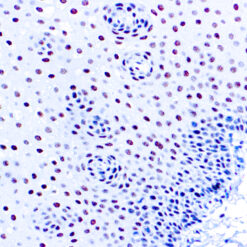

Prostate Specific Antigen, PSA

This product is intended for qualitative immunohistochemistry with normal and neoplastic formalin-fixed, paraffin-embedded tissue sections, to be viewed by light microscopy. Clinical interpretation of staining results should be accompanied by histological studies with proper controls. Patients’ clinical histories and other relevant diagnostic tests should be utilized by a qualified person(s) when evaluating and interpreting results.

| Positive Control Tissue | Prostate carcinoma |